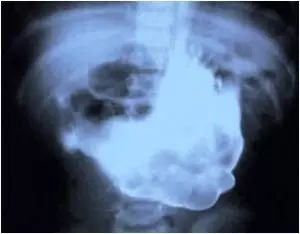

4.8岁的小女孩吞了一些东西。大家都以为是糖果之类的,看了X光之后才发现:这!是!磁!铁!

8岁的小女孩吞了一些东西。大家都以为是糖果之类的,看了X光之后才发现:这!是!磁!铁!